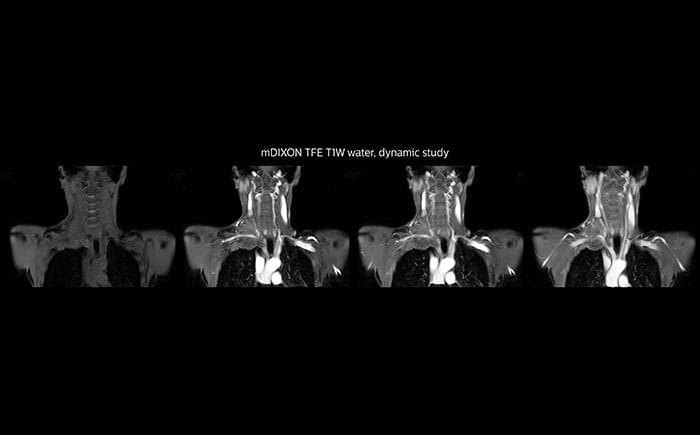

Although the area between the neck and the top of the lung is one of the most difficult areas for MRI, Prodiva 1.5T images show good quality in this 56-year-old male with Pancoast tumor on the right. mDIXON TFE images shows excellent fat suppression in the neck area and the DWI shows almost no distortion.